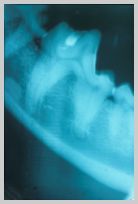

Intra-oral VD view of rostral mandible.

Crowns of premolars had been snapped off using sloppy technique

when extracting